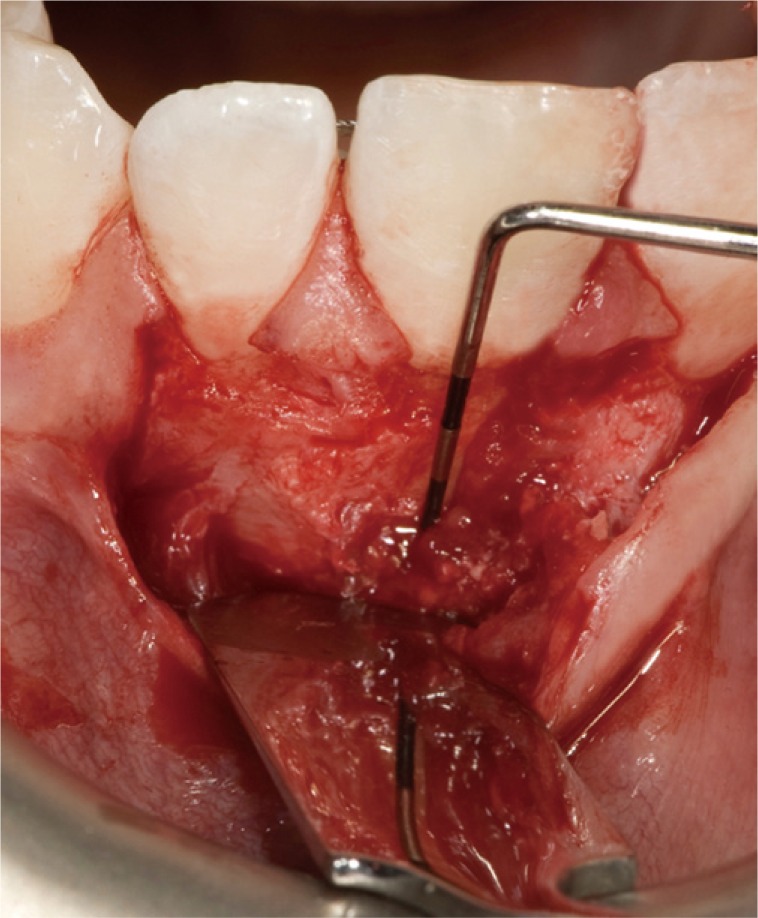

Preoperatively, the patient was fully informed about the surgical protocol and personally signed and dated the consent form before the intervention. The patient rinsed his mouth with an antiseptic mouthwash containing 0.2% chlorhexidine digluconate to reduce the risk of contamination of the surgical field. The access flap was triangular, with one horizontal incision and one vertical incision, with the latter located distally to tooth #23. A papilla base incision (PBI) approach was adopted, as described by Velvart and colleagues.14,15 Magnifying surgical loupes (×4.3) were used for enhanced visualization of the flap design and management. The flap was irrigated continuously to prevent dehydration of the periosteum.

Following flap elevation, evidence of buccal bone fenestration was clearly detected (Figure 3). The granulation tissue was removed until the anatomical structures of the exposed root portion and the alveolar bone margins were clearly visible. After exposure of the root, the type of the fracture was determined using the microscope as a magnification device. In order to detect the extent of the fracture, 1% methylene blue dye was used as a marker (Figure 4).